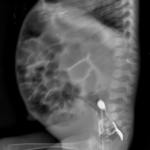

- Abdominal X-ray: Marked gaseous distension with dilated bowel loops

- Contrast enema: Suggestive of a transitional zone